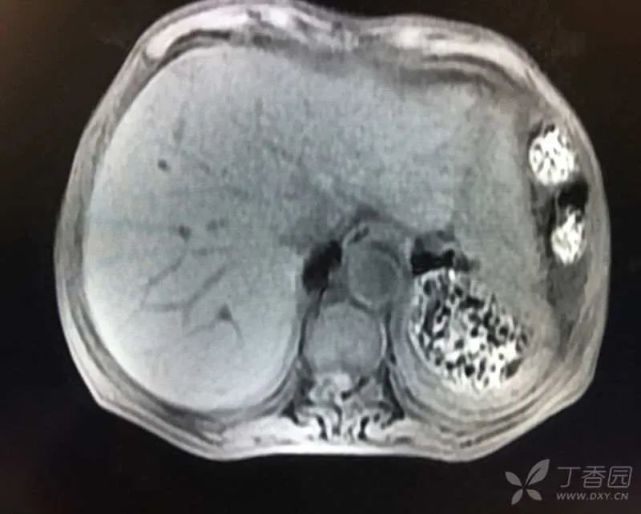

病毒全套、EBDNA、CMVDNA、ANCA、自身免疫系列、自身免疫性肝病谱、甲状腺功能均无明显异常,K-F 环阴性。MRCP:胆囊结石伴胆囊炎表现,胆总管轻度扩张,壁稍强化(炎性改变?),脾切除术后改变,肝脏再生结节形成可能性大,双肾多发小囊肿征,少量腹水(图 2)。

图片

(图 2 MRCP 检查结果)